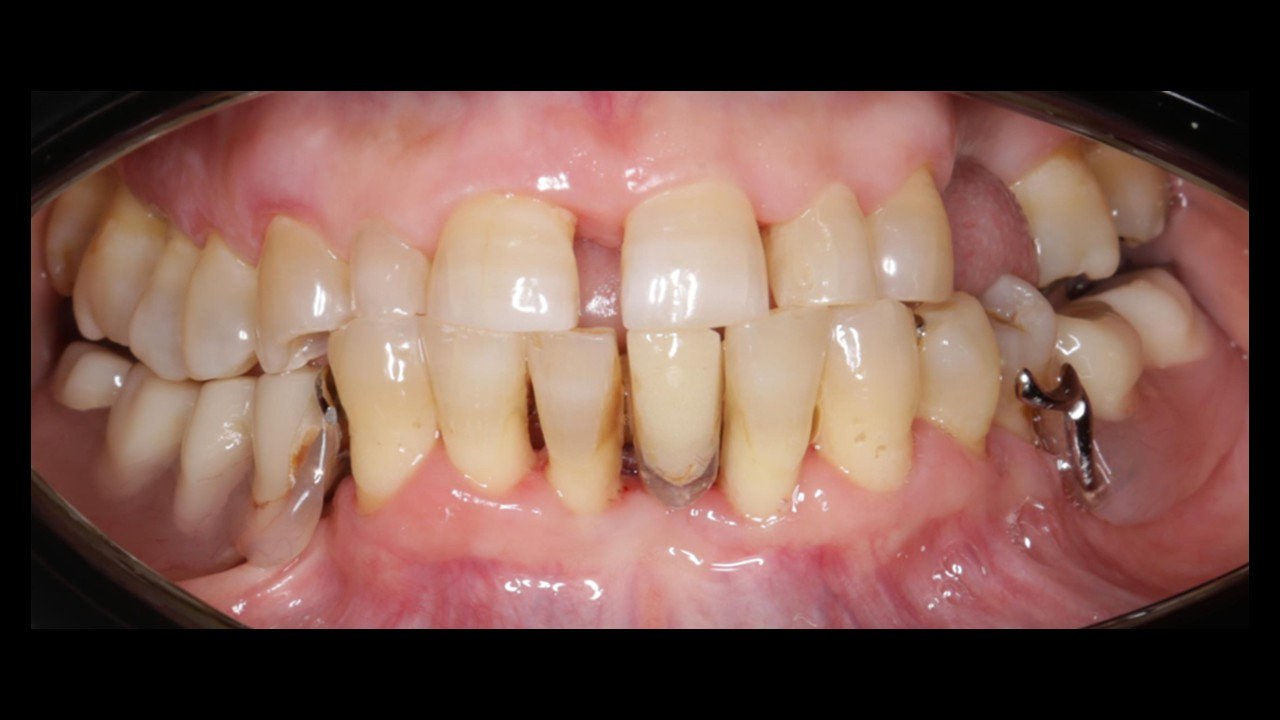

12 de diciembre de 2025 · Dr. Miroslav Andreucic

Exodoncia dientes inferiores + IOI (5)

Caso Clínico Dr. Miroslav AndreucicOdontólogo especializado en periodoncia e implantología, con más de 10 años de experiencia en salud pública y privada.Datos personales paciente:Nombre: I.J.S.Edad: 56 añosGénero: FEMA…